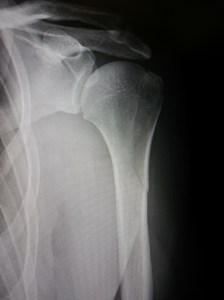

Back home, A&E done, fracture and break found and clearly seen, it’s back to the fracture clinic on Tuesday.